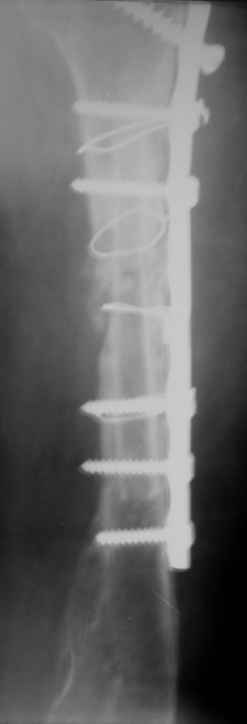

Уважаемые коллеги! На консультации больная 65 лет. С одной рентгенограммой - рис.1.

Анамнез: 30 августа перелом левой плечевой кости, невропатия лучевого нерва - кисть повисла сразу. Лечение по месту жительства - иммобилизация косынкой. 2 октября в одной из больниц города металлоостеосинтез. Все развалилось. 16 октября - повторная операция, через десять дней - картина на рис.1. Далее металлоостеосинтез с костной аутопластикой малоберцовой костью 9 февраля 2009г. Снимки 2-4 выполнены сегодня.

Считаем, что шансов на приживление и перестройку такого трансплантата в данной ситуации нет. Нестабильность запрограммирована и вываливание этого всего дело ближайшего будущего. Вопросы для обсуждения: